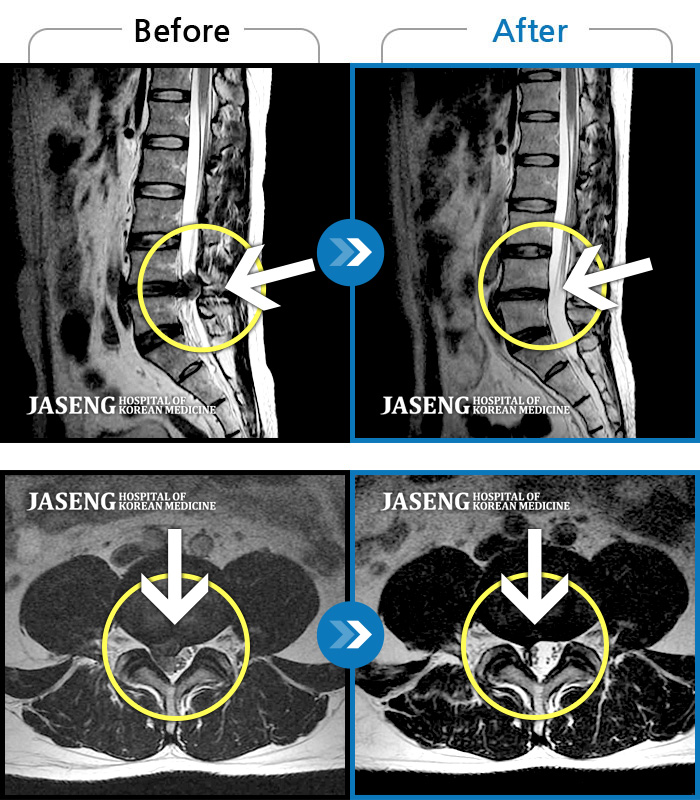

그러나 안도의 마음은 잠시뿐, 일상생활이 가능할 정도의 통증에서 벗어나, 다소 느긋한 마음으로 인터넷 검색을 하며 고농도 스테로이드 주입에 따른 부작용을 찾아보면서 다시 불안감이 엄습해왔습니다. 무엇보다 6개월 이내에 재발할 확률이 높다는 대목은 저를 초조하게 했습니다. 그러던 중 지인들로부터 평소 입소문도 듣고, 같은 직장 선배가 진료를 보고 효과를 보고 있다고 추천을 해 준 자생한방병원을 찾게 되었습니다. 평소 한의원, 한방요법들에 대한 불신이 컸던 저로서는 반신반의의 선택이었습니다. 그때만 해도 시술 후 수영과 조깅 등 운동만으로도 유지가 가능할거라는 자신감도 있었기 때문이었습니다. 그러나 초기상담에서 저의 MRI 촬영사진을 보며 김기원원장님의 상세한 설명을 듣고, 제가 시술받았던 척추전문병원에서도 설명을 듣지 못했던 중요한 부분들에 대해 추가로 알게 되었습니다. 허리상태가 생각보다 좋지 않다는 것과 알지 못했던 목디스크도 같이 있다는 것을 알게 되면서 치료, 관리가 꼭 필요하다는 마음을 굳힐 수 있었습니다. 또한 추나요법을 받으면서 비지땀을 흘리며 수기치료를 하시는 원장님을 보면서 진심으로 진료를 하시는구나 하는 생각과 함께 치료에 대한 믿음이 생겼습니다.

그 결과 현재는 앉고 일어설 때의 통증과 불안정감이 확연히 줄었고, 일상생활에 큰 불편감 없이 생활하고 있습니다. 처음 진단받았을 때의 좌절감이 아닌, 새로운 희망으로 생활하고 있습니다. 이대로 유지만 된다면 더 이상 병원에 오지 않아도 되지 않을까 하는 생각이 들 정도의 건강을 회복했고, 주변에서 좋아 보인다는 말을 자주 듣고 있습니다. 이제서야 드는 생각이지만 처음 허리를 펴지 못할 정도의 극심한 통증을 겪었을 때, 인근의 양방병원이 아닌, 자생한방병원으로 바로 갔으면 스테로이드 주입술 없이도 건강을 회복할 수 있지 않았을까 하는 아쉬움이 큽니다. 그래서 저는 요통을 경험하는 직장 동료들과 지인들에게 주저하지 않고 자생한방병원을 권합니다.